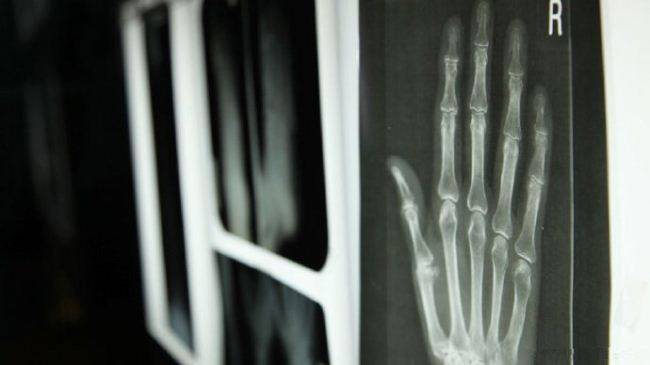

骨骼框架:27 块骨头的 “灵活组合”

解剖画面清晰展示,人类的手由 27 块骨头组成(8 块腕骨、5 块掌骨、14 块指骨),这些骨头通过关节连接,形成 “多维度活动” 的基础 —— 腕骨如 “万向节”,能让手掌灵活转动;掌骨支撑手掌形态,指骨则可实现屈伸、内收外展等动作。例如,拇指的 “鞍状关节”(腕掌关节)是人类手部的 “独特设计”,能让拇指与其他四指相对(即 “对掌运动”),这一动作在动物界极为罕见,却是人类能握笔、使用工具的关键。George McGavin 博士在片中演示:“没有对掌运动,我们无法握住杯子、系鞋带,更无法发明与使用复杂工具,人类文明的进步,从某种程度上说,是‘手的功能’的延伸。”